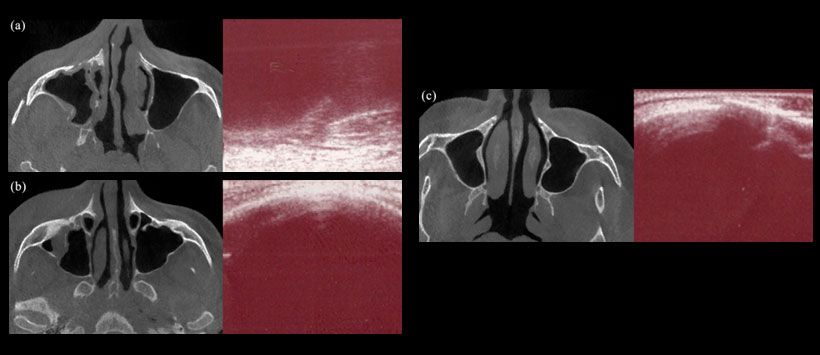

Un total de 120 órbitas con sospecha clínica de fracturas aisladas del suelo orbital se sometieron a una tomografía computarizada multicorte con reconstrucción coronal; ecografía orbital utilizando una máquina estándar equipada con un transductor lineal de 7 a 10 MHz (Figura 1) ; y CBCT (Figura 2).

Según los hallazgos de la TC, las fracturas del piso estaban presentes en 39 órbitas. La sensibilidad, la especificidad, el valor predictivo positivo y el valor predictivo negativo de la ecografía para detectar fracturas del piso orbital fueron 87.2%, 100%, 100% y 94.2%, respectivamente. Los valores correspondientes para CBCT fueron 97.4%, 97.5%, 95.0% y 98.8%, respectivamente. Las áreas bajo las curvas de características del operador receptor de la detección de fractura del piso orbital fueron 0,94 para ecografía y 0,98 para CBCT.